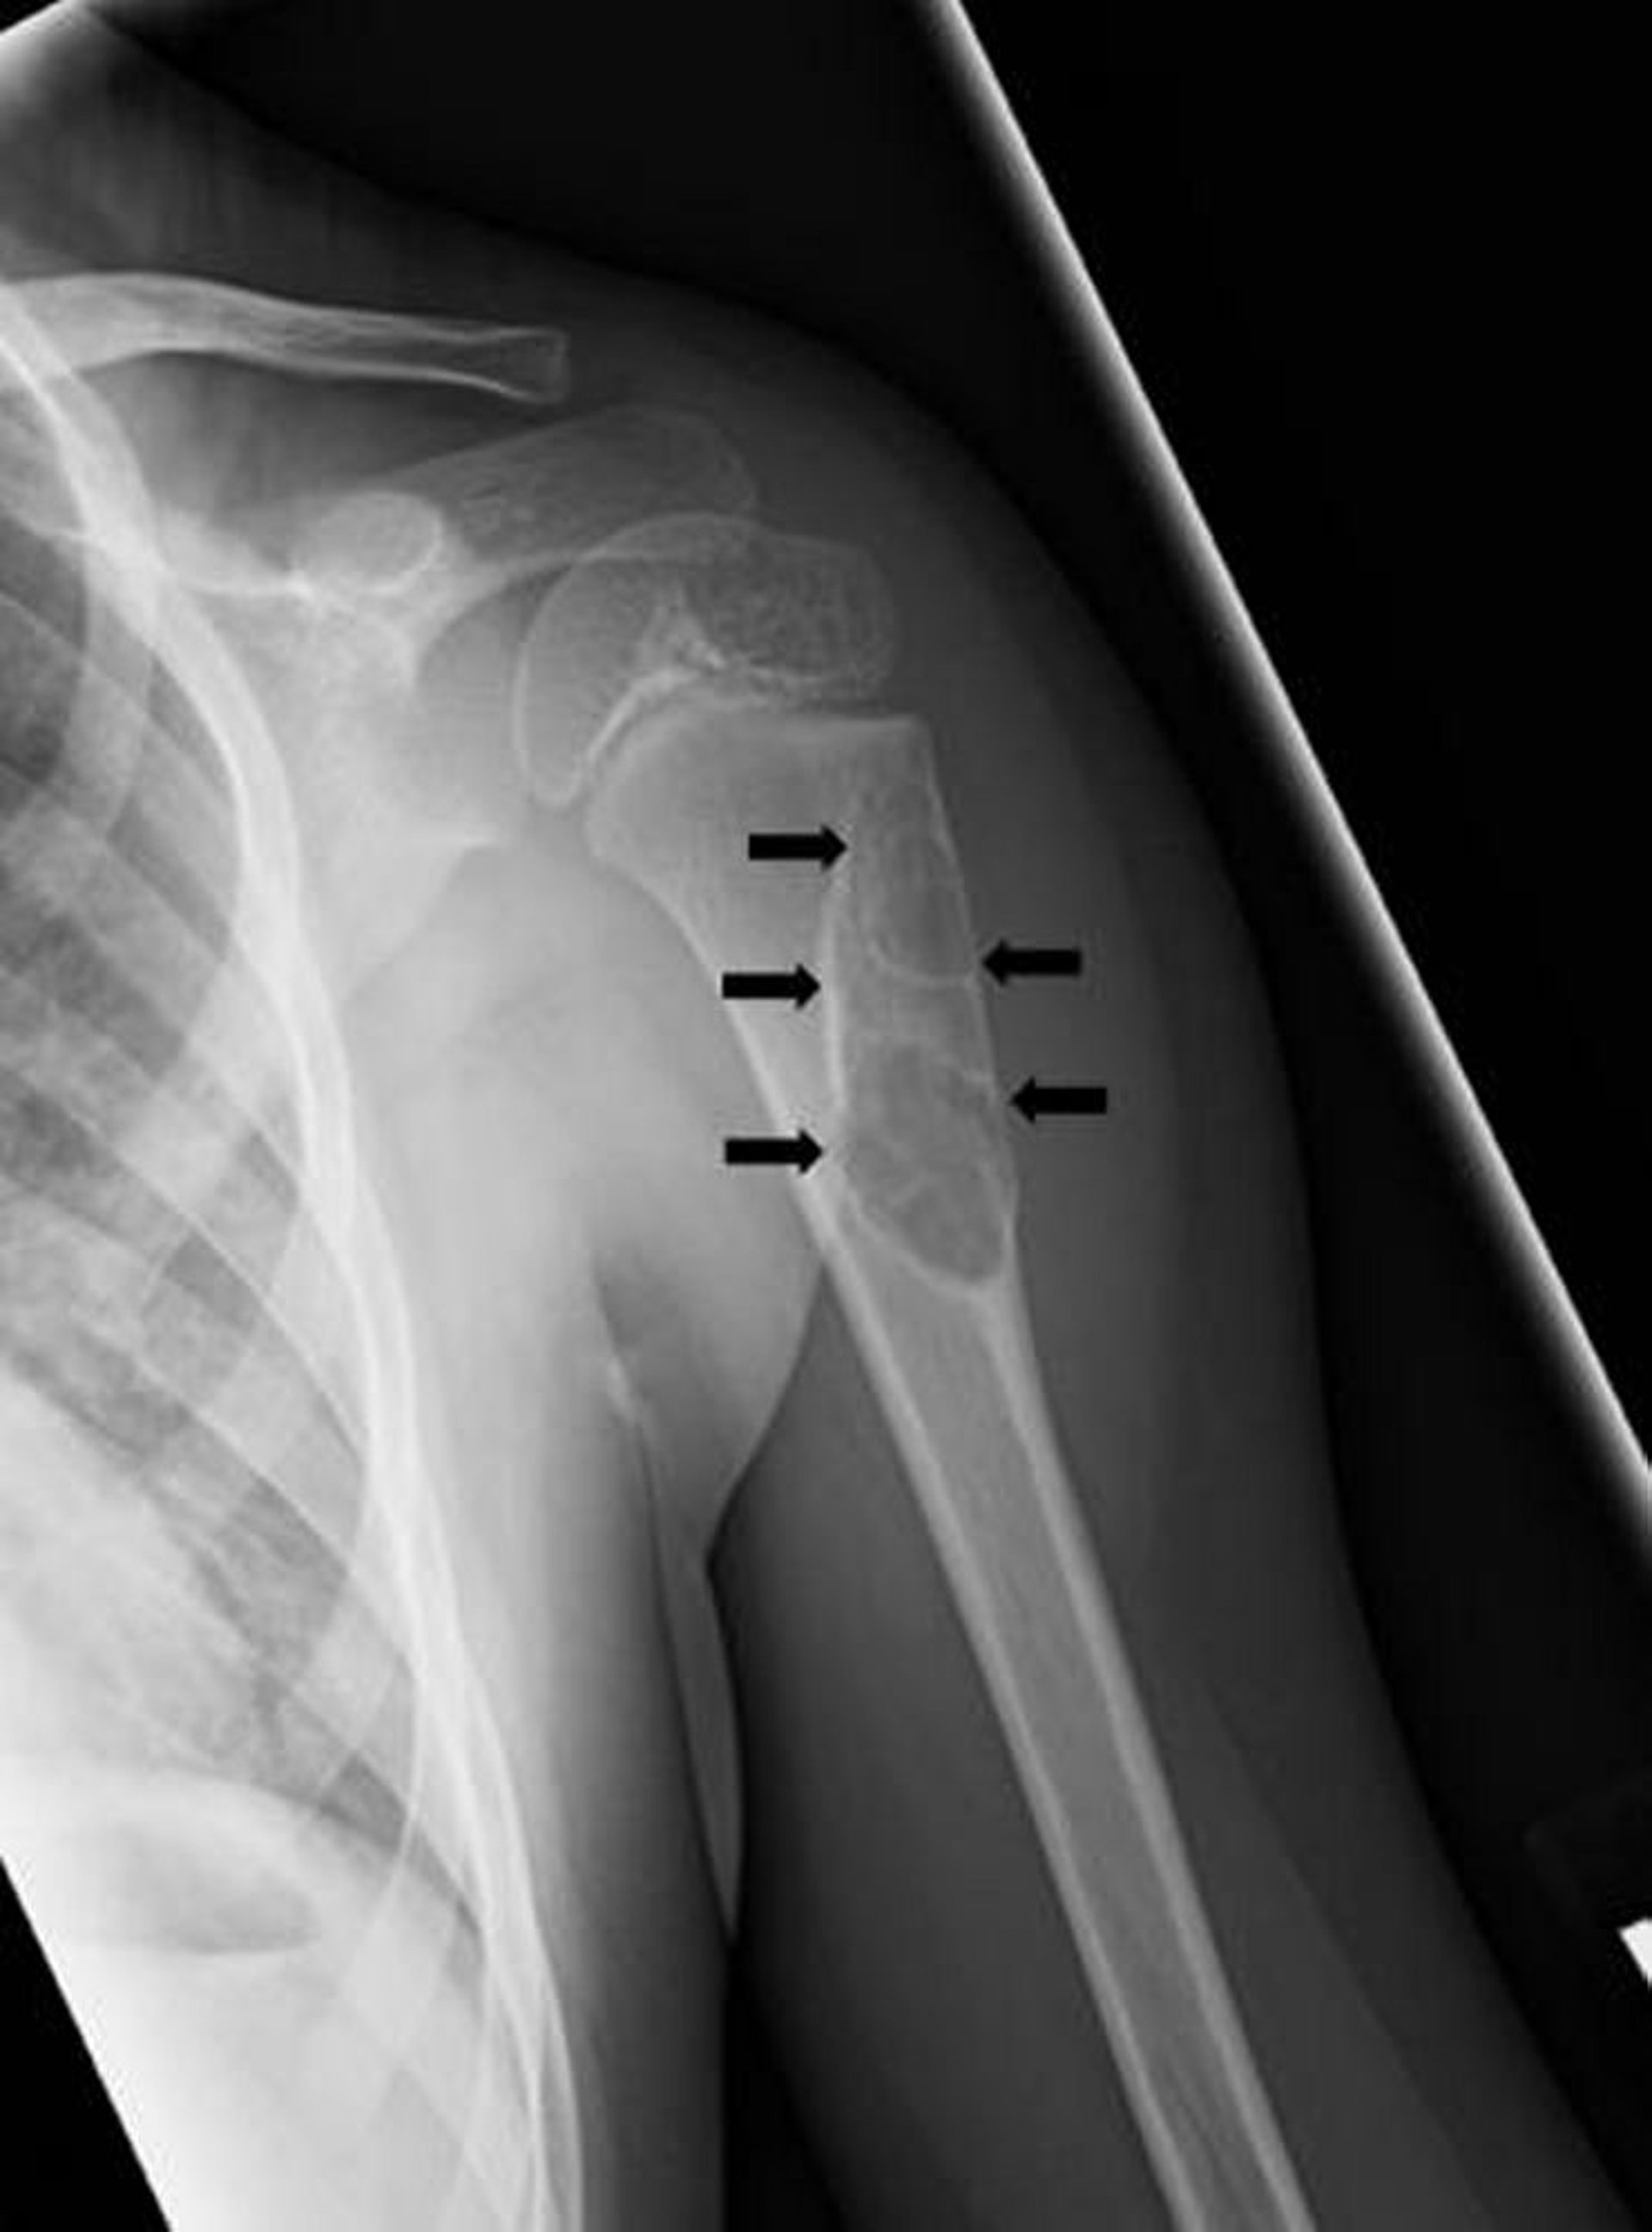

Radiografia che mostra una cisti ossea unicamerale (frecce) nell’osso del braccio.

Per gentile concessione di Michael J. Joyce, MD e Hakan Ilaslan, MD.